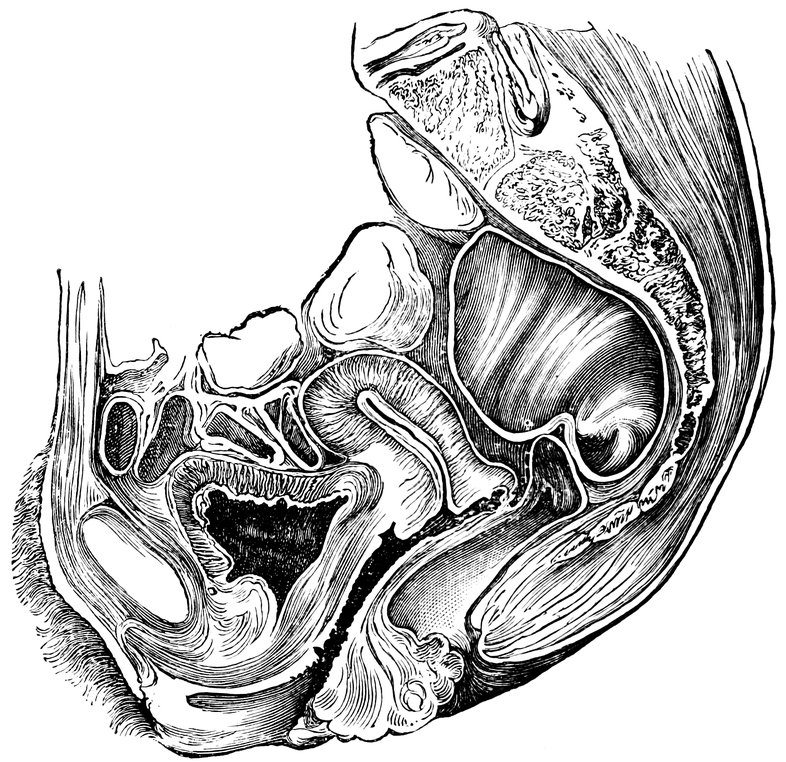

| 14. | Sagittal section of the female pelvis | 56 |

| 51. | Female internal genital organs in the fully developed state | 208 |

Fig. 2.—Portion of the pelvic viscera in the female, and their relation to the muscles of the pelvic outlet (or perineal muscles), shown in the left half of the pelvis, seen from the right side.—The parametrium. (From Toldt: Atlas of Human Anatomy.—Rebman Company, New York.)